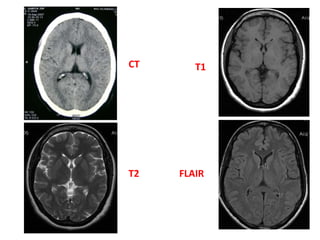

CT

FLAIRT2

T1

FLAIR & STIR SEQUENCES

T1 W Images: SubacuteHemorrhage Fat-containing structures Anatomical Details T2 W Images: Edema Tumor Infarction Hemorrhage FLAIR Images: Edema, Tumor Periventricular lesion WHICH SCAN BEST DEFINES THE ABNORMALITY

• 24.

T1W AND T2W IMAGES